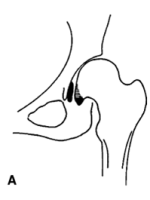

下图可见假髋臼和髂骨骨赘